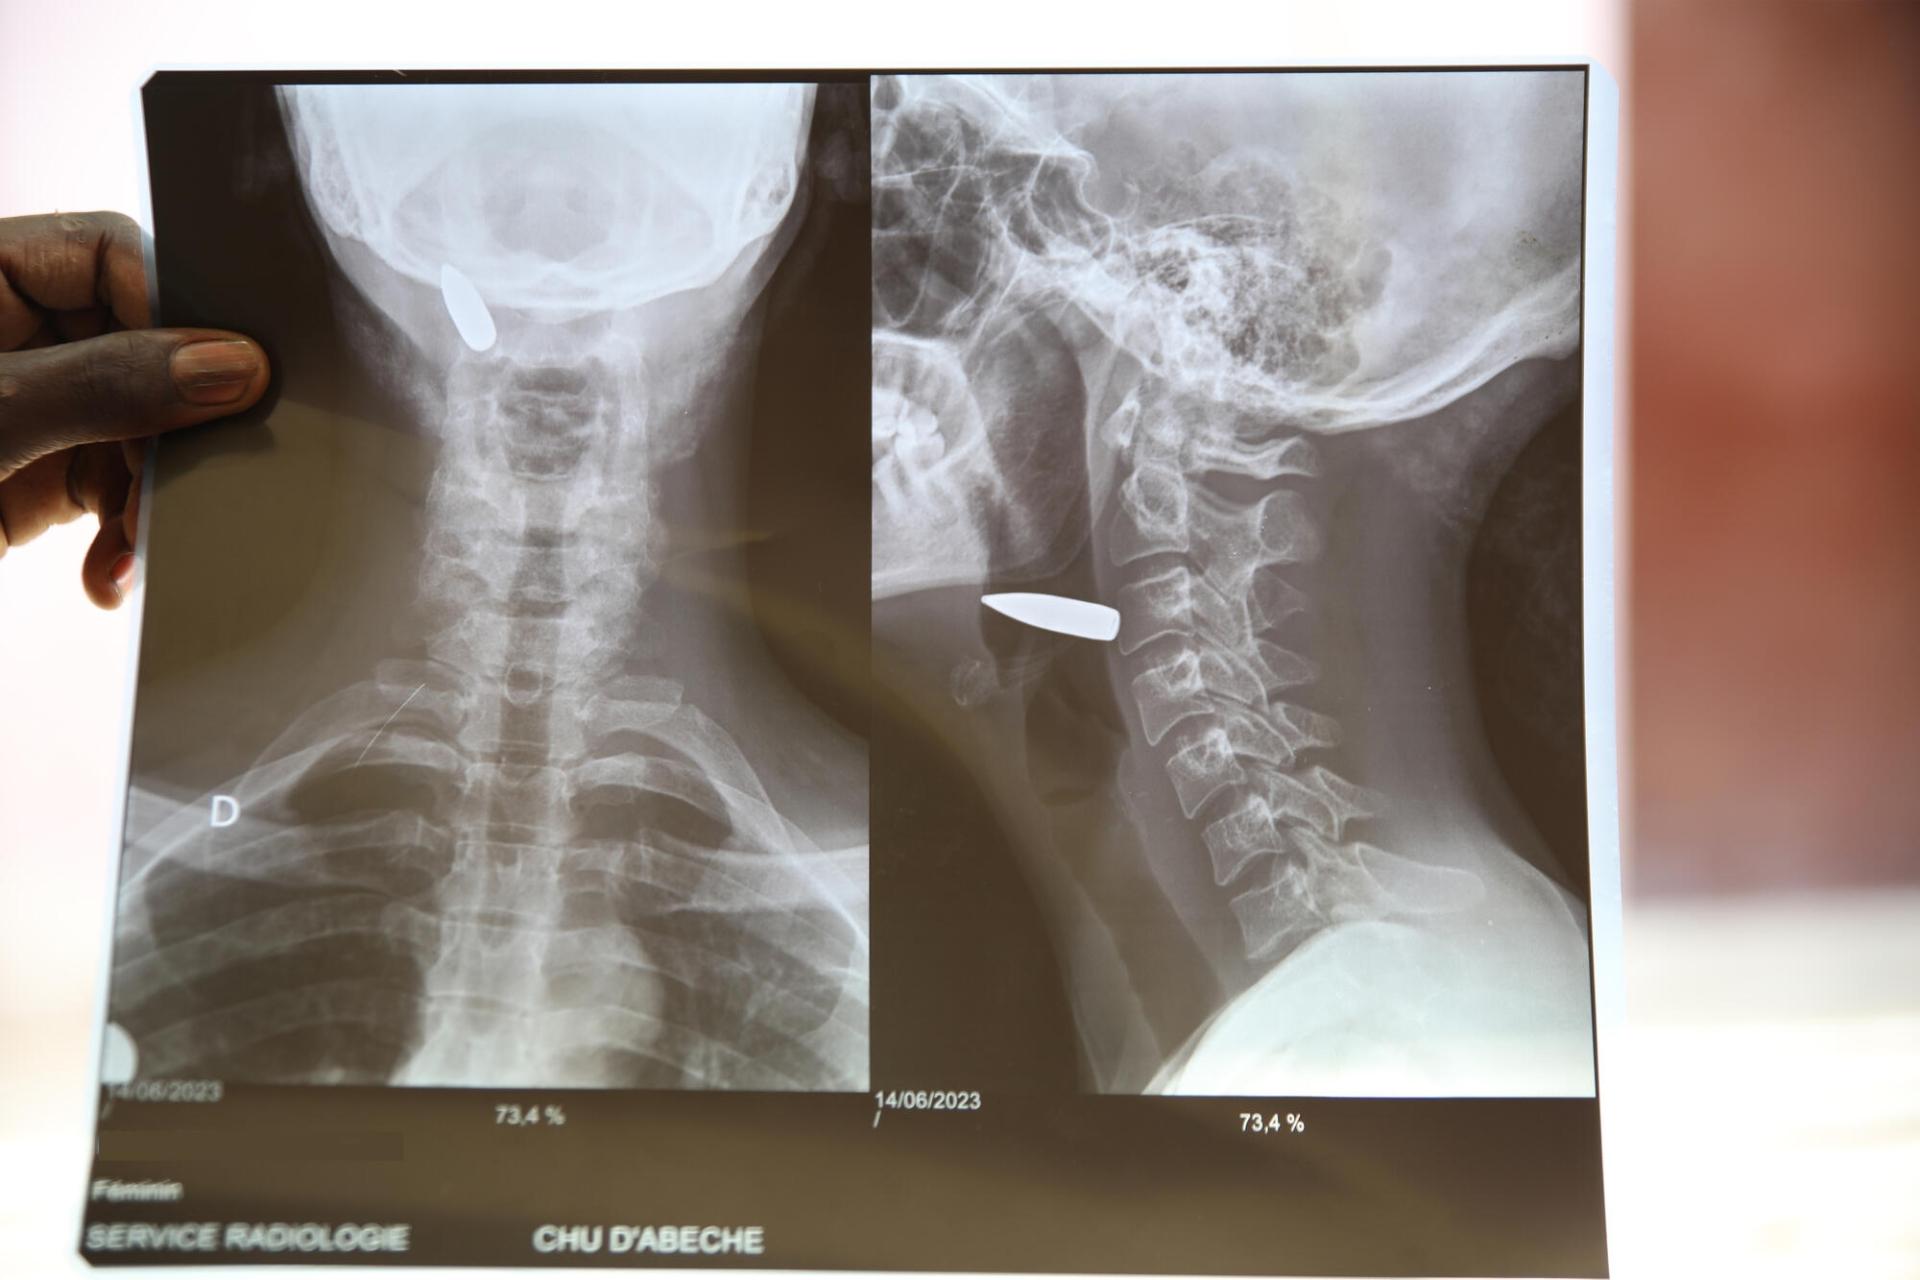

Radio d'une femme ayant reçu une balle dans le cou

Radiographie de la blessure par balle soignée par MSF à l'hôpital d'Abéché.

Tchad. Juin 2023.

© Mohammad Ghannam/MSF

Cette femme qui a reçu une balle dans le cou a été prise en charge à l'hôpital d'Abéché.

Une réfugiée Soudanaise blessée par balle au cou a été prise en charge par MSF à l'hôpital d'Abéché.